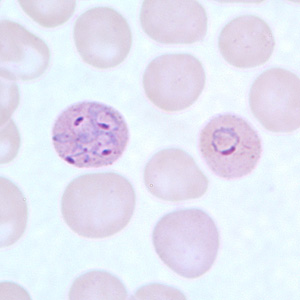

P. vivax

P. ovale

P. malariae

P. falciparium

Babesia